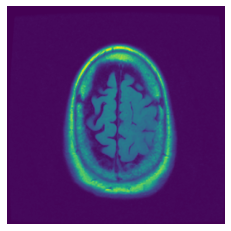

In figure 3, we present qualitative examples of different masking strategies. It is observed that, unlike context prediction and restoration, our method tends to propose targeted masks like the tumor regions or regions with abnormalities and avoids masking less helpful regions. However, it should be noted that Intelligent-Masking does not necessarily mask the tumor regions but considers all areas of interest that results in better feature learning. Examples of other masking samples are provided in supplementary materials. Furthermore, in medical images, unlike natural scenes, the structures are very local with imbalanced information throughout an image. Therefore, random masking strategies as shown in Fig 3 operate ineffectively by masking non-informative regions.

Figure 2: Qualitative examples of compared method’s strategies for masking

Figure 3: More qualitative examples of different distorting strategies including our method. We show the different self-supervised mechanisms on both datasets of MR (rows: 1-3) and ultrasound (rows: 4-6) images for lower-grade glioma and breast cancer diagnosis respectively. We include both images of normal (rows: 1,4) and cancer (rows: 2,3,5,6) conditions for each dataset. We also observe that our method treats each image based on its context information with no predetermined strategy.